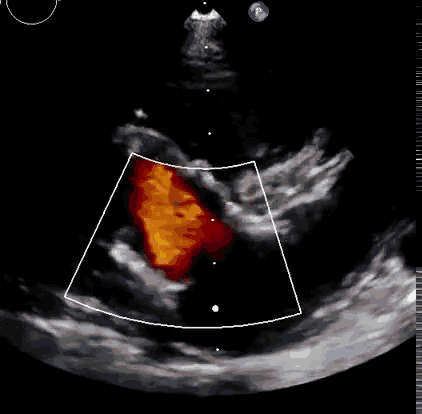

本次臨床前研究經(jīng)右側(cè)頸靜脈置入LuX-Valve Plus輸送系統(tǒng)可調(diào)彎鞘管,在DSA及超聲引導(dǎo)下將人工三尖瓣瓣膜植入到原有三尖瓣位置,利用獨(dú)特的錨定技術(shù)將人工瓣膜支架可靠固定在預(yù)定的位置。

上海中山醫(yī)院葛均波院士、錢(qián)菊英院長(zhǎng)、周達(dá)新教授、潘文志教授、潘翠珍教授、李偉教授共同完成此次臨床前研究。術(shù)后葛均波院士對(duì)Lux-Valve Plus的器械操作性能給予了高度評(píng)價(jià),DSA和超聲影像也顯示出在本次研究中Lux-Valve Plus的安全性和有效性俱佳。